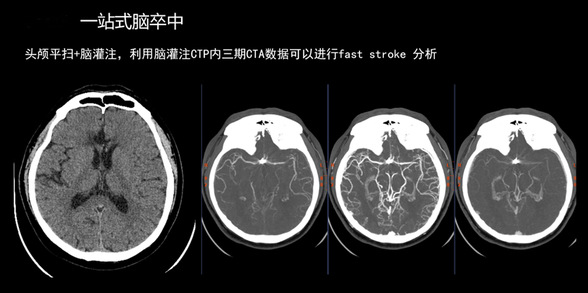

在卒中救治中,除了明确血管堵塞位置,更需要判断脑组织是否还有挽救余地。为在最短时间内获取最全面信息,团队果断为赵先生开具了“头颈部CTA”及“颅脑灌注分析(CTP)”联合检查。

能否快速准确完成影像评估,是决定患者预后的关键。赵先生被迅速送入放射影像诊断中心,一场由Revolution Apex超高端CT主导的“精准侦察”随即展开。这台被誉为“火眼金睛”的设备在极短时间内完成高质效扫描:

1、速度之快:一次扫描完成血管形态和脑组织灌注双重评估,将影像检查时间缩短至几分钟,真正实现“快”字当头。